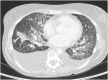

We present a case of a 47-year-old woman with a history of asthma and mononeuritis who presented with shortness of breath and fatigue. Heart failure was diagnosed and echocardiography revealed large floating thrombi attached to the left ventricular walls. Cardiac magnetic resonance imaging showed evidence of myocarditis and angiitis. Blood count revealed eosinophilia. She was diagnosed with eosinophilic granulomatosis with polyangiitis or Churg-Strauss syndrome (CSS) according to recently updated criteria. Medical management with specific aetiology (anticoagulation or immunosuppression) and heart failure treatment resulted in clinical improvement. We further discuss the diagnostic approach of CSS with cardiovascular complications and therapeutic management.